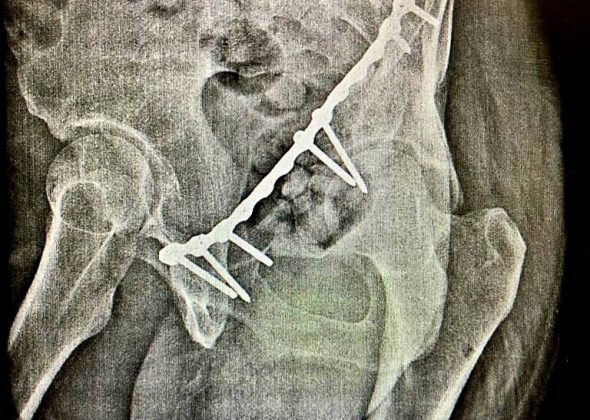

Мужчина был направлен из Домодедовской городской больницы в травматологическое отделение ГБУЗ МО «Раменская областная больница» с целью оперативного лечения вертлужного перелома костей таза со смещением бедра. В отделении травматологии пострадавшему была произведена компьютерная томография костей таза и принято решение о необходимости оперативного лечения. Хирурги-травматологи блестяще провели сложную операцию по устранению смещения бедренной кости и восстановлению вертлужной впадины, после чего пациент смог встать на костыли.

«В перспективе мы прогнозируем у пациента полное восстановление тазобедренного сустава и возможность передвижения без ограничений. Являясь травмоцентром первого уровня, мы часто принимаем пациентов из близлежащих районов с переломами костей таза, которым необходимо оперативное лечение», — рассказал заведующий травматологическим отделением ГБУЗ МО «Раменская областная больница» Всеволод Владимирович Ушанов.